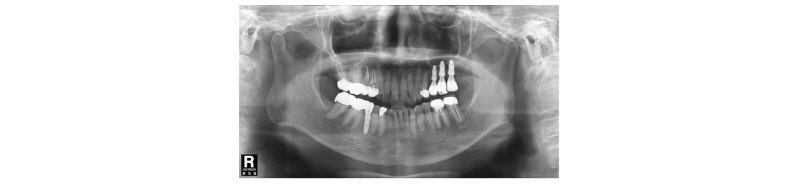

Fig. 19. First visit. Panoramic x-ray view. |

70세의 여자환자로 상악에 사용하던 부분틀니가 불편하다고 호소하시며 내원하였다. 부분 틀니의 지대치인 상악 좌측 견치 또한 보철물 하방으로 우식이 진행되어 보철물 제거후 우식치료 후 보철물을 재제작하여 장착하기로 계획하였다. 치아가 결손되어 있던 상악 좌측 소구치와 대구치 부위는 임플란트 식립(#24i-26i, 27i)을 통한 고정성 보철물 수복을 계획하였다(Fig. 19). 장기간의 부분틀니 장착으로 인해 임플란트 식립 예정 부위의 심한 치조제 흡수가 관찰되었으며 특히 소구치 부위가 가장 흡수 정도가 심하였다(Fig. 20). 전층판막 형성 후 상악 좌측 제 1 소구치 부위는 치조정에서 약 2 mm 정도의 매우 좁은 치조제 폭경이 확인되었다(Fig. 21). 먼저 상악 좌측 제 1 소구치 부위 치조정에 horizontal intraosseous groove를 작게 형성한 후 협측골에 근, 원심 양측에 vertical intraosseous groove를 형성하였다(Fig. 22). Chisel을 이용하여 협측 골판을 조금 확장시킨 다음 spreader drill (RS kit, Dentium, Korea)을 단계적으로 이용하여 충분히 확장시켜 임플란트 식립을 위한 공간을 확보하였다(Fig. 23). 분리된 협,설측 골판 사이 공간으로 Ø4.3 × 10 mm (Implantium, Dentium, Korea) 임플란트를 식립하였다(Fig. 24). 상악 좌측 대구치 부위는 상악동 거상술(측방접근법)을 시행하여 #26i, 27i : Ø4.3 × 10 mm, Ø4.8 × 10 mm (Implantium, Dentium, Korea)를 식립하였다(Fig. 25). 식립된 24i 임플란트와 협,설측 골판 사이의 gap에 합성골 (Osteon II, Xenoss, Korea)을 적용한 다음 협측 골판 상방에 콜라겐함유 합성골(Osteon II Collagen, Xenoss, Korea)을 추가적으로 적용하였고 식립된 26i, 27i 임플란트 부위의 협측골 두께가 얇아서 협측골 상방에도 콜라겐함유 합성골(Osteon II Collagen, Xenoss, Korea)을 적용하였다(Fig. 26). 골이식재 상방에 흡수성 교원질 차폐막(Collagen, Xenoss, Korea)을 피개한 후 감장절개를 통해 장력없이 봉합하였다(Fig. 27, 28). 약 10일 후 발사 시의 임상소견으로 정상적으로 치유가 잘 진행되었다(Fig. 29). 술 후 파노라마 방사선 소견으로 치조제 분할술을 통해 식립된 24i 임플란트와 상악동 거상술(측방접근법)을 시행하여 식립된 26i, 27i 임플란트가 확인되었다(Fig. 30). 4개월 치유 후 이차 수술 시 전층 판막거상 후 협측으로 충분히 증가된 치조제 폭경과 식립된 임플란트 주위에 이식한 골이 혼화되어 치유된 양상이 확인되었고 치유지대주를 연결하였다(Fig. 31). 이차 수술 후 치유가 정상적으로 진행되어 통법에 따라 보철 수복하였다. 보철물 수복 직후 방사선 사진 소견으로 식립된 24i 임플란트의 변연골 위치가 확인되었다(Fig. 32). 보철물 장착 후 1년 후 방사선 소견에서 임플란트 주위 변연골이 안정적으로 잘 유지되고 있었다(Fig. 33). 보철물 장착 4년 후 follow- up 결과 임플란트 주위 치은이 약간 퇴축된 양상을 보였으나 임상적으로 특이한 소견이 관찰되지 않았고 방사선 소견에서 임플란트 주위 변연골이 안정적으로 잘 유지되고 있음을 확인하였다(Fig. 34-36).